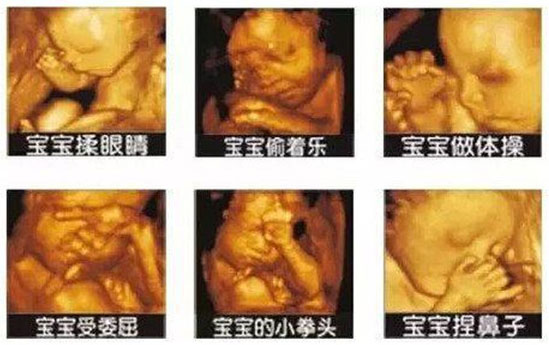

四维彩超,可协助医生直接对胎儿先天畸形进行诊断,能确定胎儿在子宫中的精确位置。另外,四维彩超在普通B超的基础上增加了时间维度参数,可以实时观察胎儿动态的活动图像。

四维彩超的功能非常强大,与普通B超相比,彩超有良好的成像效果。胎宝宝在腹中的动态举止,通过彩超可以清楚直观的查看到。包括胎宝宝的一言一行、一举一动,如打哈欠、微笑、生气、发怒、犯困等状态,都可以看得清清楚楚。